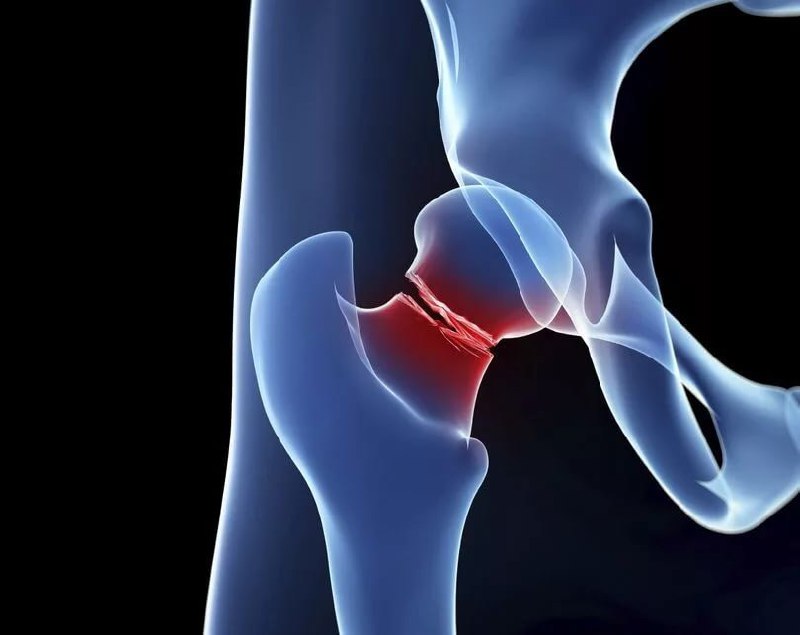

Travma veya yüksek enerjili kazalar sonucunda oluşan bir durumdur. Kemiklerin dayanıklılığı genç yaşlarda daha güçlü olsa da, trafik kazası, spor yaralanması gibi şiddetli darbeler yol açar. Gençlerde kalça kırığı genellikle cerrahi müdahale ve rehabilitasyon ile gerçekleştirilir. Gençlerde iyileşme süreci genellikle daha hızlıdır, ancak doğru tedavi önemlidir.

Kalça veya kasık bölgesinde yoğun ağrı hissedilir. Bu ağrı genellikle hareketle artar. Kırık olan kalçanın hareket ettirilmesi zorlaşır ve yürümek imkansız hale gelebilir. Kırığın olduğu bölgede şişlik ve morluklar oluşabilir.

Bacak diğerine göre daha kısa görünebilir veya dışa doğru dönebilir. Kalçaya ağırlık vermek zorlaşır, ayağa kalkmak ve ayakta durmak acı verici olabilir. Erken teşhis ve tedavi önemlidir çünkü gençlerde kalça kırığı bile ciddi komplikasyonlara yol açabilir.